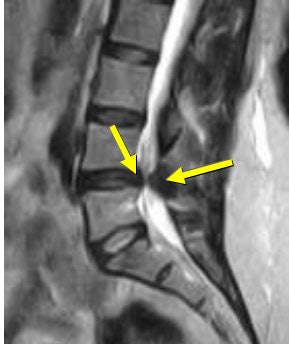

| Same patient as above. Top, transaxial T2-weighted image showed left L4 spinal nerve root compromise with axial loading (below). |

Willen and Danielson have also shown that axial-loaded imaging, during recumbent MRI or CT, simulates weight-bearing forces in the lumbar spine, provoking narrowing of the central spinal canal and neural foramina, and increasing the diagnostic accuracy of dynamic spinal stenosis. Dynamic stenosis has been defined in literature as a change in the cross-sectional dural sac area of greater than 15 mm² resulting in a decrease in the dural sac area to less than 75 mm (Spine, December 1, 2001, Vol. 26:23, pp. 2607-2614; Acta Radiologica, November 1998, Vol. 39, 6, pp. 604-611; Spine, December 1, 2001, Vol. 26:23, pp. 2601-2606).

Willen and Danielson's group found that 79% of patients with combined low back and leg symptoms experienced a significant reduction of the dural sac cross-sectional area during axial compression; 35% of patients passed the borderlines for relative stenosis (100 mm²) or absolute stenosis (75 mm²); 36% of patients experienced deformation of the dural sac during axial compression; and 13% of patients experienced a narrowing of the lateral recess during axial compression (Spine, December 15, 1997, Vol. 22:24, pp. 2968-2976).